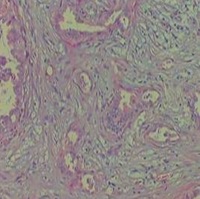

3.肝外胆管癌的组织学类型:根据癌细胞的类型分化程度及癌组织生长方式肝外胆管癌可分为以下6型:

②高分化腺癌:在胆管癌中最多可占2/3以上可见于任何部位癌组织均在管壁内浸润生长环绕整个管壁浸润的癌组织呈大小不等形状不规则的腺体结构有的可扩大呈囊腔

③低分化腺癌:即分化差的腺癌癌组织部分呈腺体结构部分为不规则的实性片块亦在管壁内弥漫浸润生长